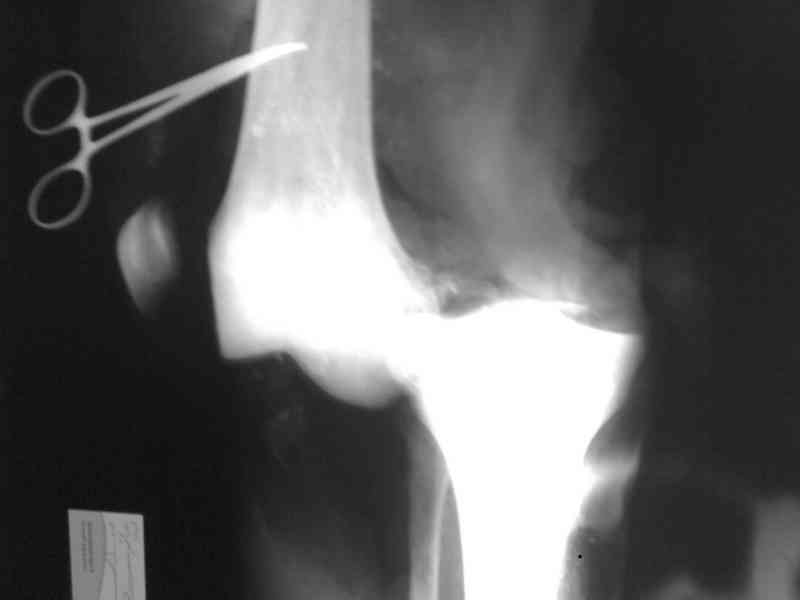

Снимки прошлых публикации из моего Power point

На ренгенограмме хорошая аппозиция костей коленного сустава, но надколенник находится подозрительно высоко, поэтому необходимо убедиться в отсутствии повреждения связки надколенника.

Наличие пульсации на конечностях еще не доказательство отсутствия интимальных повреждении сосудов, наблюдались вторичные осложнениия, поэтому важна консультация сосудистого специалиста.